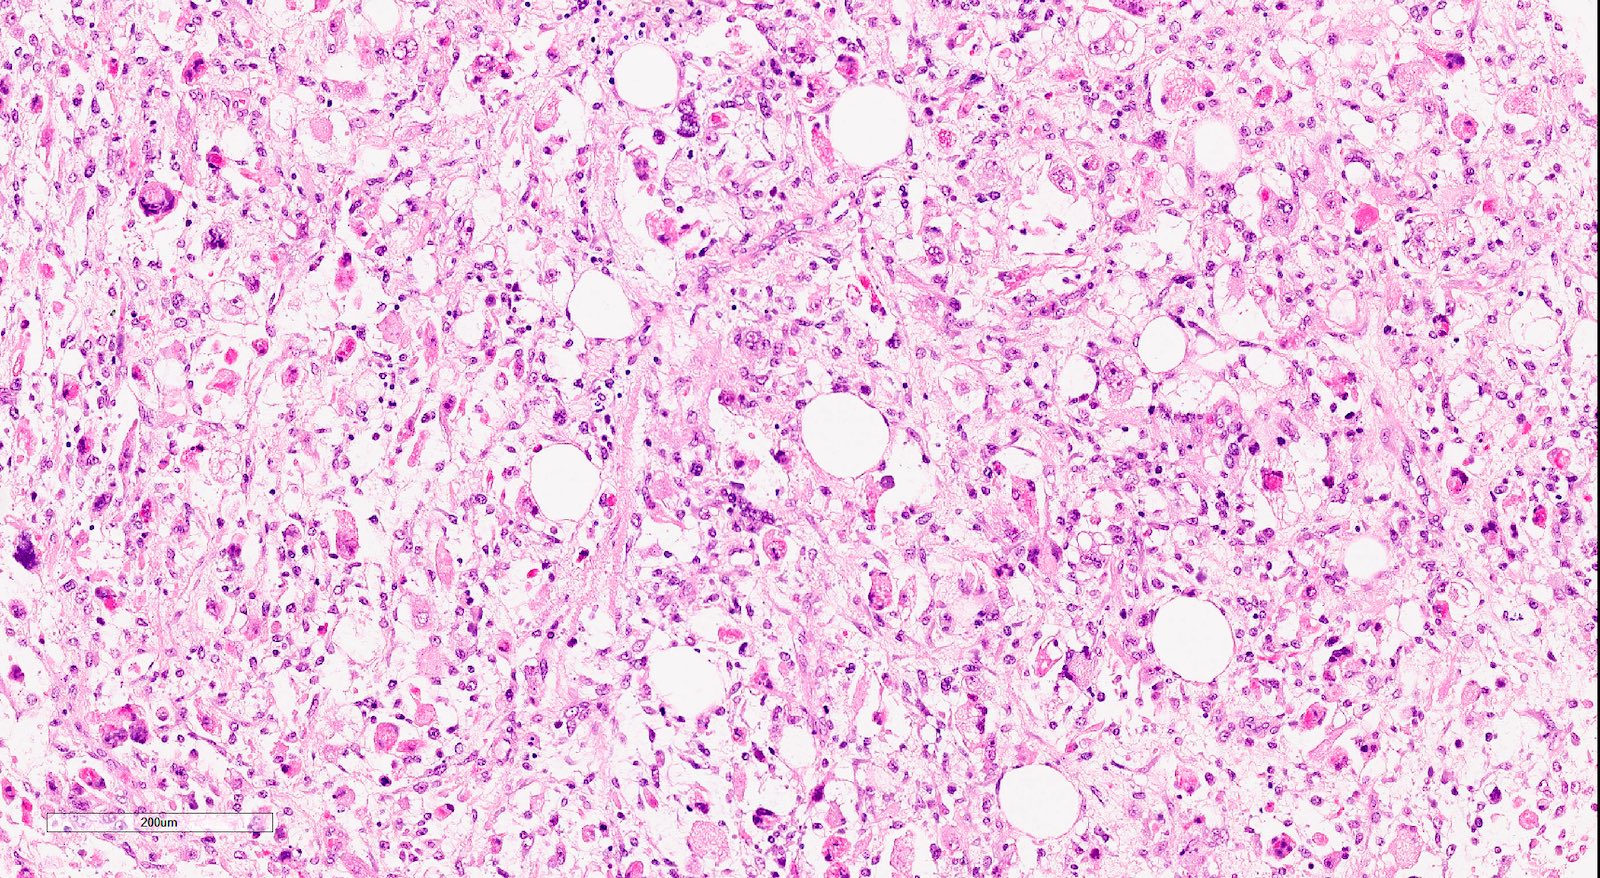

Microscopic (histologic) description

- Biphasic tumor with carcinomatous and sarcomatous elements, both high grade (Int J Gynecol Pathol 1990;9:1)

- Carcinomatous and sarcomatous components are juxtaposed

- Sarcomatous elements:

- Often spindle and pleomorphic

- 50% contain heterologous elements (most commonly rhabdomyosarcoma and chondrosarcoma) (Am J Surg Pathol 2007;31:1653)

- Osteosarcomatous, liposarcomatous and angiosarcomatous differentiation are less common (Semin Diagn Pathol 1988;5:199, Arch Pathol Lab Med 1991;115:583, Int J Gynecol Pathol 2017;36:140)

Microscopic (histologic) images